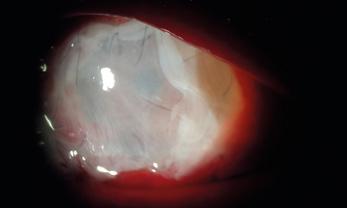

La queratitis ulcerativa periférica (QUP) es una lesión inflamatoria y destructiva del estroma y epitelio corneal yuxtalimbar que lleva a un adelgazamiento progresivo de la córnea. En su etiopatogenia están involucrados desórdenes inmunológicos favorecidos por la vasculatura perilimbar. Muchas veces cursa con escasa sintomatología, por lo que puede llegar a la perforación sin que el paciente sea consciente de ello.

La QUP puede aparecer de forma aislada o estar asociada a una enfermedad sistémica, siendo los síndromes vasculíticos los más frecuentes.

En estos casos, la QUP puede ser la primera manifestación de la enfermedad sistémica siendo la afectación ocular un signo de mal pronóstico ya que expresa actividad de la enfermedad.

La granulomatosis con poliangeitis asociada a ANCA C+ (exenfermedad de Wegener) es una vasculitis granulomatosa necrotizante sistémica, potencialmente letal, que puede afectar los tejidos oculares. En su manejo, son fundamentales el diagnóstico precoz y un tratamiento adecuado.

Paciente masculino de 48 años de edad se presenta en la guardia oftalmológica refiriendo leve dolor y molestias en el ojo izquierdo de aproximadamente 1 mes de evolución. A la anamnesis dirigida, el paciente menciona como antecedente: anemia y nefropatía en estudio.

AVMC: OD: 10/10

OI: 2/10

Bomicroscopia:

OD: inyección conjuntival mixta, úlcera corneal periférica con forma de media luna de horas 7 a 11.

OI: inyección conjuntival mixta, úlcera periférica de horas 12 a 5, con perforación a horas 3, protrusión de iris.

FO: sin particularidades en AO.

Se realiza interconsulta con reumatología y se decide intervención quirúrgica urgente de reparación primaria con parche escleral y recubrimiento conjuntival en OI, y solo recubrimiento conjuntival en OD, que se realiza el mismo día.

Luego de la cirugía, se inicia tratamiento sistémico con meprednisona 40mg/día, vía oral. El paciente presenta buena evolución a las 24 horas de postoperatorio.

En los exámenes de laboratorio solicitados por reumatología, el paciente presenta anemia, proteinuria, microhematuria, ANCA C+, diagnosticándose granulomatosis con poliangeitis asociada a ANCA C+. A los 10 días, el paciente presenta nueva úlcera corneal periférica inferior en OD, por lo que reumatología indica pulsos de metilprednisolona y posteriormente tratamiento inmunosupresor con ciclofosfamida. En los días siguientes evoluciona de forma desfavorable presentado adelgazamiento corneal periférico en AO. Se interviene nuevamente al paciente realizando recubrimiento con membrana amniótica bilateral.

En los controles presenta una evolución favorable con membrana amniótica aplicada que se reabsorbe a los 10 días –aproximadamente– en ambos ojos. Se observa franca mejoría de la superficie, transparencia, espesor e inflamación corneal.

Al mes de la última cirugía, el paciente continúa con enfermedad inactiva, asintomático y córnea en condiciones estables. Se realiza seguimiento por reumatología con tratamiento inmunosupresor mediante pulsos de ciclofosfamida.